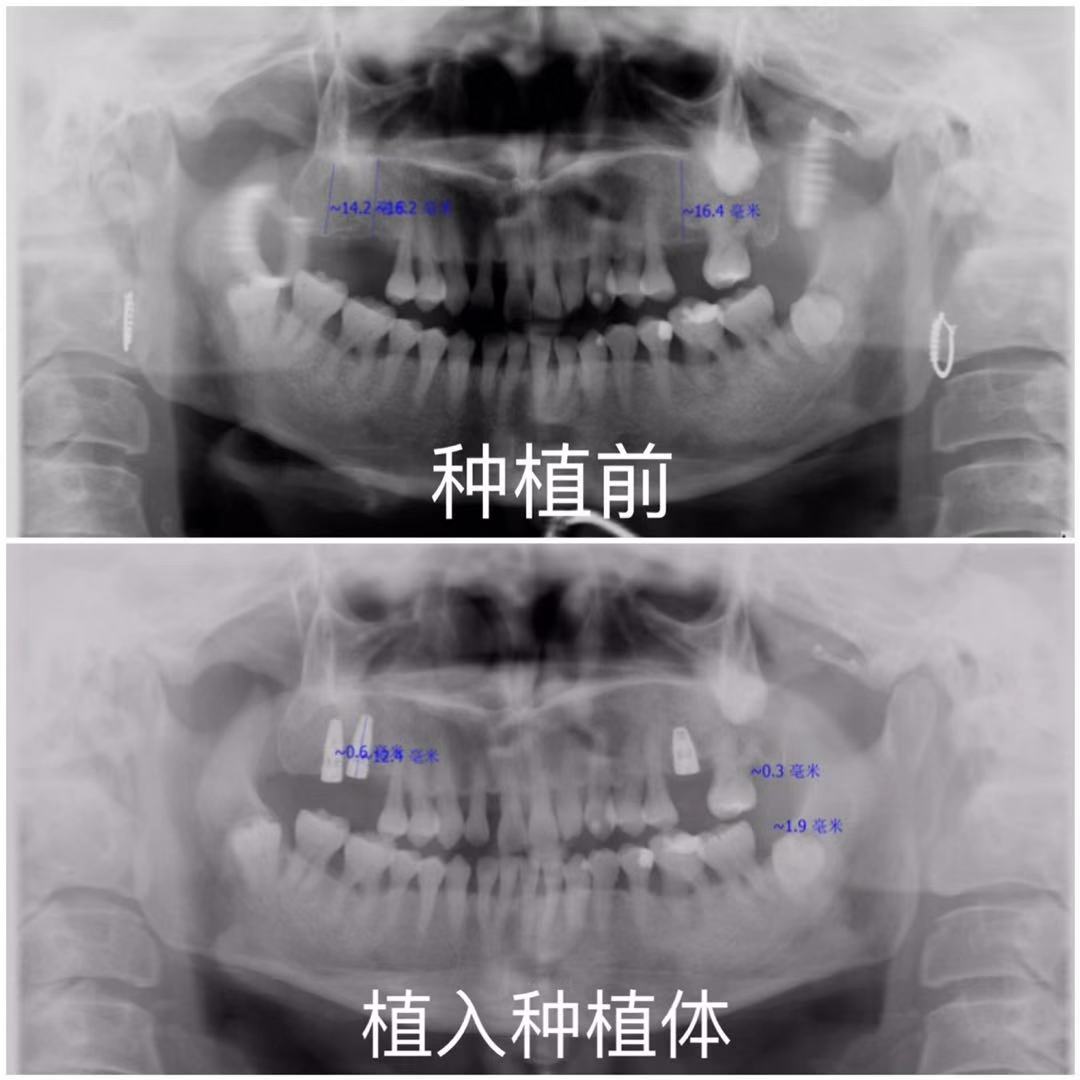

• 多颗牙缺失该如何补救?

吃喝玩乐是人生当中最大的乐趣,而吃是首要大事,如果我们不能尽情吃喝的话,生活便会...

• 女53岁+ 多颗缺失李耀华医生

• 单颗牙缺失一年,怎样修复

牙齿缺失的痛苦,只有感同身受才会明白!特别是年轻人,年纪轻轻就失了牙,很是有损形...

• 男25岁+ 单颗缺失武玉锦医生